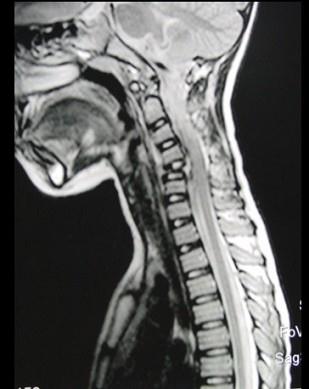

问题 男,37岁,主诉颈部疼痛,活动时加重,休息后疼痛可减轻,夜间盗汗等,请结合所提供图像,选出最佳答案 ( )

选项 A、颈椎结核 B、骨髓瘤 C、颈椎骨转移 D、颈椎退行性变 E、骨巨细胞瘤

答案 A